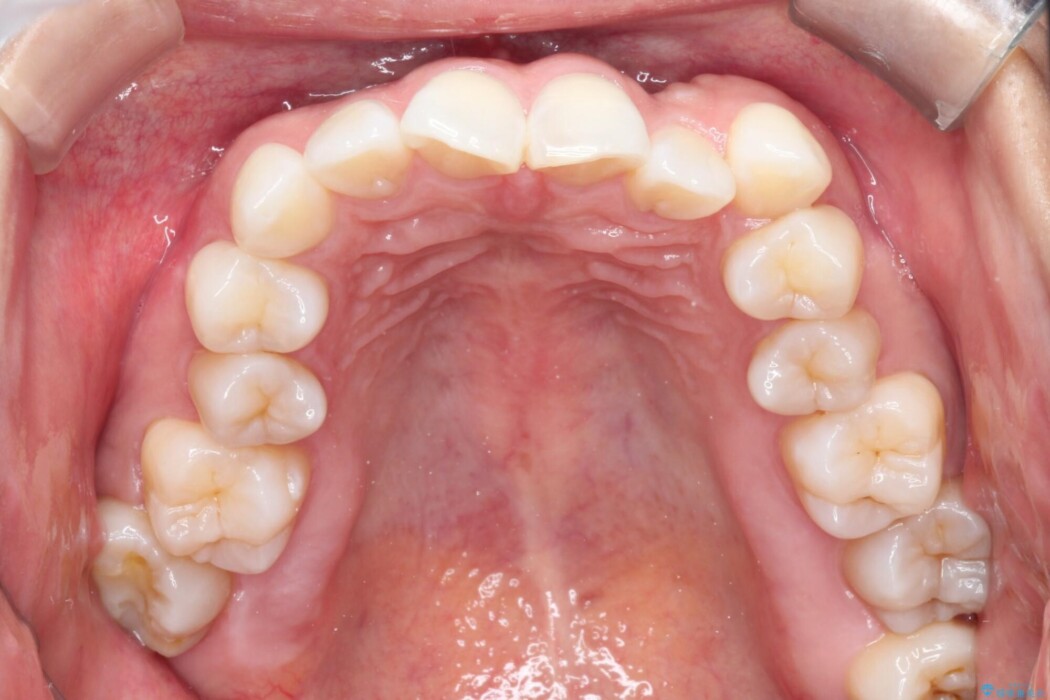

上下のガタつきと、右上の奥歯が外側に飛び出して上下が正しく噛み合わないシザーズバイトの改善のためにご来院された患者様です。

矯正検査の結果、右上7番が頬側に大きくズレており、うまくかみ合っていない状態でした。

全体的にスペース不足ではありましたが、患者様は抜歯をしたくないとのご要望だったため、上顎の裏側に「トランスパラタルアーチ(TPA)」という装置を装着し、奥歯の幅を調整しながらスペースを確保する計画を立案。